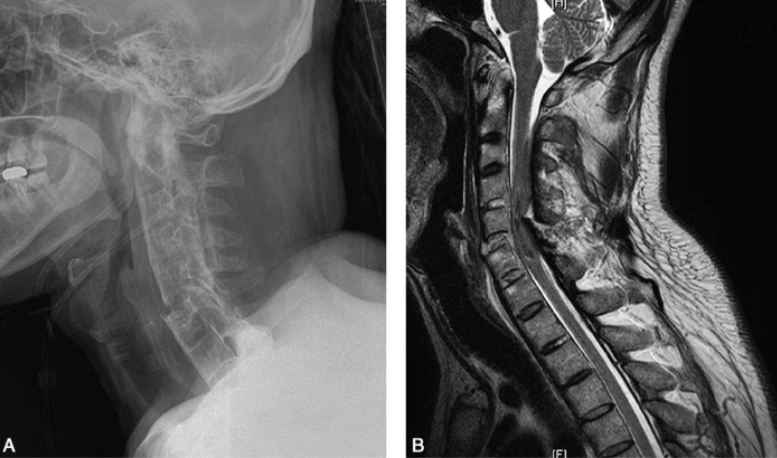

图3 颈椎强直性脊柱炎男,38岁。

A. 颈椎侧位X线片显示颈椎椎体方形椎。外伤后C6椎体骨折,上颈椎后移;

B. 颈椎矢状位MRI T2WI显示C6椎体骨折,局部呈片状长T2信号,C5~6水平颈髓损伤,韧带骨化。

关节周围骨髓内脂肪蓄积,当病变进一步发展,在骶髂关节面两侧均可出现脂肪蓄积,此时T1WI和T2WI可显示片状高信号区,而于脂肪抑制即显示为低信号;病变中后期,病变可呈不同程度的骨性强直,关节间隙可从变窄,到关节间隙消失,增生的骨小梁T2WI信号减低。对于强直性脊柱炎患者外伤成像可较X线提供更多的信息(图3)。